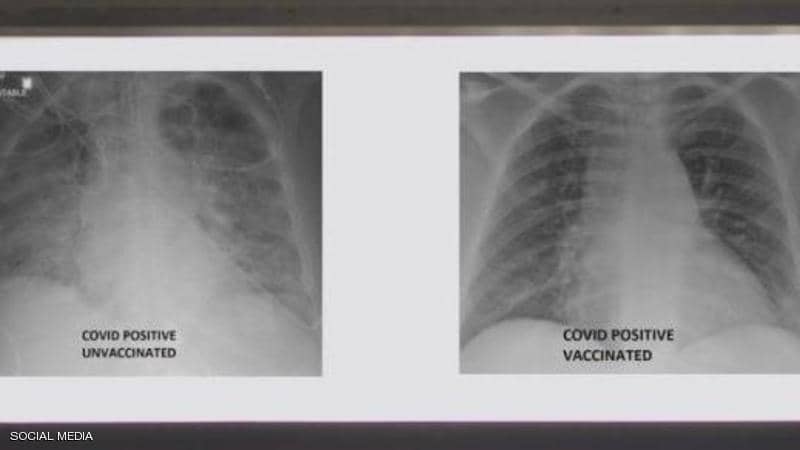

صور أشعة توضح الفرق بين رئتي شخص مطعم ضد كورونا وآخر غير محصن

نشر الطبيب العربي في الولايات المتحدة، غسان كمال، صورة تظهر الفرق بين رئتي شخص جرى تطعيمه ضد فيروس كورونا ورئتي شخص آخر لم يتلق التطعيم، مشيرا إلى أن الاثنين أصيبا بفيروس كورونا.

وأظهرت صور الأشعة السينية، أن رئتي الشخص غير الملقح، المصاب بفيروس كورونا كانت بيضاء بصورة شبه كاملة وتعرف بـ"عتامة الرئة"، مما يعني أنها كانت غارقة في الفيروس، في حين أبرز صور رئتي الشخص ببيضاء أقل.

وتعني صورة الأول أيضا نقصا في دخول الهواء إلى رئتيه، فيما تعني لدى الثاني أن الهواء يتدفق بسهولة علاوة على أن رئتيه خاليتين من الوباء.

وأشار إلى أنه نشر الصور من أجل إظهار الفرق الذي يمكن أن يحدثه اللقاح في رئتي الشخص في حال إصابته بالفيروس، وهذا حتى يتعرف الجميع على الآثار التي تظهر على الرئة نتيجة اللقاح.